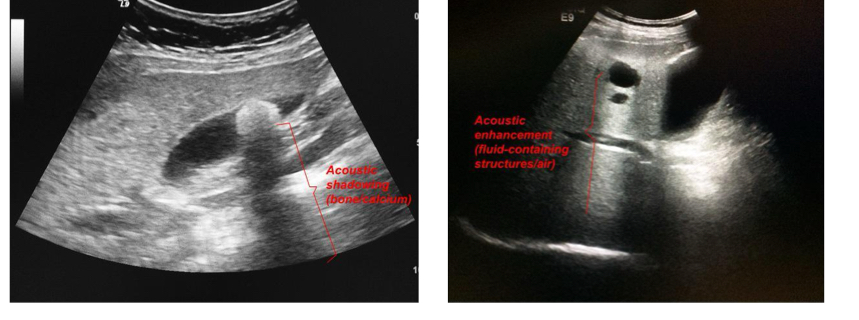

What is posterior acoustic shadowing and what is posterior acoustic enhancement?

Shadowing occurs when there is a region that doenst le US go thruCalci in kidney and gallbladder cause posterior acoustic shadowing, hepatic cyst (cystic structure typically fillled with liquid) shows posterior acoustic enhancement.